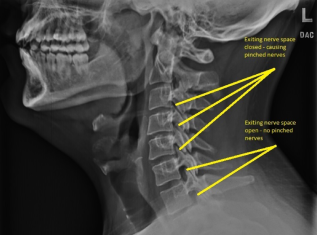

Digital X-Ray

At Dr. Asher Natural Chiropractic We have a new state of the art digital X-ray machine that is able to accomodate patients from all walks of life. We pride ourselves in the identification and treatment of spinal disorders, but we are also able to accomodate and evaluate upper and lower extremities with our advanced tilting X-ray bucky.

Advertisement

Call us today at 504-336-2707 to schedule a free consultation, where we will review your cervical or lumbar MRI and explain to you why your body is sending signals of pain to your back, legs, neck, or arms. After reviewing your MRI we will go over how we can help decrease the bulging disc material in your spine and get you back to moving again without pain, numbness, and weakness. Please have your MRI on a CD for review upon arrival. Dr. Asher will go over the images on the CD with you instead of reading the report to show you first hand why your body is in pain.